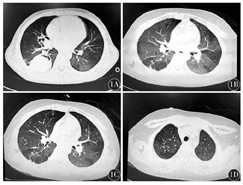

患儿,男性,11岁,以确诊白血病27个月,反复发热1个月,头痛5 d为主诉于2014年9月25日入住我院。入院前27个月因确诊为ALL(B细胞型,中危型)。诱导化疗期间有侵袭性肺曲霉病病史(图1A)。入院前1个月出现发热,伴有畏冷、寒战,无咳嗽,无气促。血常规示:白细胞计数(WBC)5.29×109/L,中性粒细胞绝对值(ANC)4.62×109/L,血红蛋白(Hb)115 g/L,血小板计数(Plt)198×109/L,C反应蛋白(CRP)79.47 mg/L;降钙素原(PCT)0.17 ng/ml;γ-干扰素释放试验技术(IGRA)、结核感染T细胞检测(T-SPOT)、抗结核抗体、真菌葡聚糖、半乳甘露聚糖试验、EB病毒(EBV)-DNA、巨细胞病毒(CMV)-DNA、肺炎支原体抗体均阴性;肺部CT示双肺可见散在淡薄片状影,透亮度明显减低(图1B);考虑肺部感染(细菌、真菌混合感染可能性大,卡氏肺孢子虫不能排除),予亚胺培南西司他丁+万古霉素+复方磺胺甲噁唑抗感染及卡伯芬净抗真菌2周,甲泼尼龙(2 mg/kg×7 d)抗感染治疗,体温恢复正常,复查肺部CT较前稍有吸收。入院前5 d再次发热,伴有咳嗽、头痛、呕吐;头颅+肺部CT检查示:双肺炎症,纵隔可见肿大伴钙化淋巴结(图1C),左上颌窦窦腔内可见丝状密度影;予头孢哌酮舒巴坦+阿奇霉素抗感染,卡伯芬净抗真菌,更昔洛韦抗病毒,症状无改善。既往无肺结核病史及接触史,有按时进行预防接种。体格检查:体温36.5 ℃,脉搏90次/min,呼吸21次/min,血压102/68 mmHg(1 mmHg=0.133 kPa),体质量38 kg,神志清楚,营养中等,呼吸平稳。右上臂可见卡疤,全身浅表淋巴结未触及肿大,双侧鼻窦区无明显压痛,颈软,心肺腹部查体无阳性体征,双侧巴氏征、克氏征阴性。

入院后骨髓常规示:粒系增生减低,吞噬细胞0.01;IGRA 102.3 pg/ml(参考值<14 pg/ml);肺部CT示:双上肺可见散在斑片影,较前增多(图1D);治疗上改为美罗培南+万古霉素抗感染,两性霉素B脂质体抗真菌,停更昔洛韦,仍反复高热,头痛加剧,并出现呕吐、颈项强直,行腰部穿刺检查。脑脊液常规示:有核细胞计数745×106/L,单个核细胞百分比9%,多个核细胞百分比91%,红细胞少许/HP;脑脊液生化检查示:葡萄糖0.95 mmol/L,氯110.0 mmol/L,脑脊液蛋白3 582 mg/L,腺苷脱氨酶(ADA)16.0 U/L;脑脊液结核杆菌TB-DNA:104拷贝/ml;脑脊液结核分枝杆菌培养阳性,对链霉素、异烟肼、利福平、乙胺丁醇均敏感。颅脑磁共振成像(MRI)未见明显异常。考虑继发性肺结核合并TBM,但细菌、真菌感染亦不能排除,予加用异烟肼+利福平+吡嗪酰胺(HRZ)抗结核,继续美罗培南(40 mg/kg,1次/8 h)抗感染,伏立康唑抗真菌,甲泼尼龙(每天0.5 mg/kg)抗感染,呋塞米、甘露醇脱水降颅压等治疗1周后,症状缓解,复查脑脊液,WBC逐渐下降至正常,脑脊液结核杆菌TB-DNA阴性,多次复查肺部CT及颅脑MRI提示炎症逐渐吸收,继续HRZ抗结核治疗3个月后再次开始白血病维持化疗,同步以HRZ抗结核维持1年2个月。随访至截稿前,患儿白血病已停药2年仍处于持续完全缓解,抗结核化疗停药1.5年未出现复发。